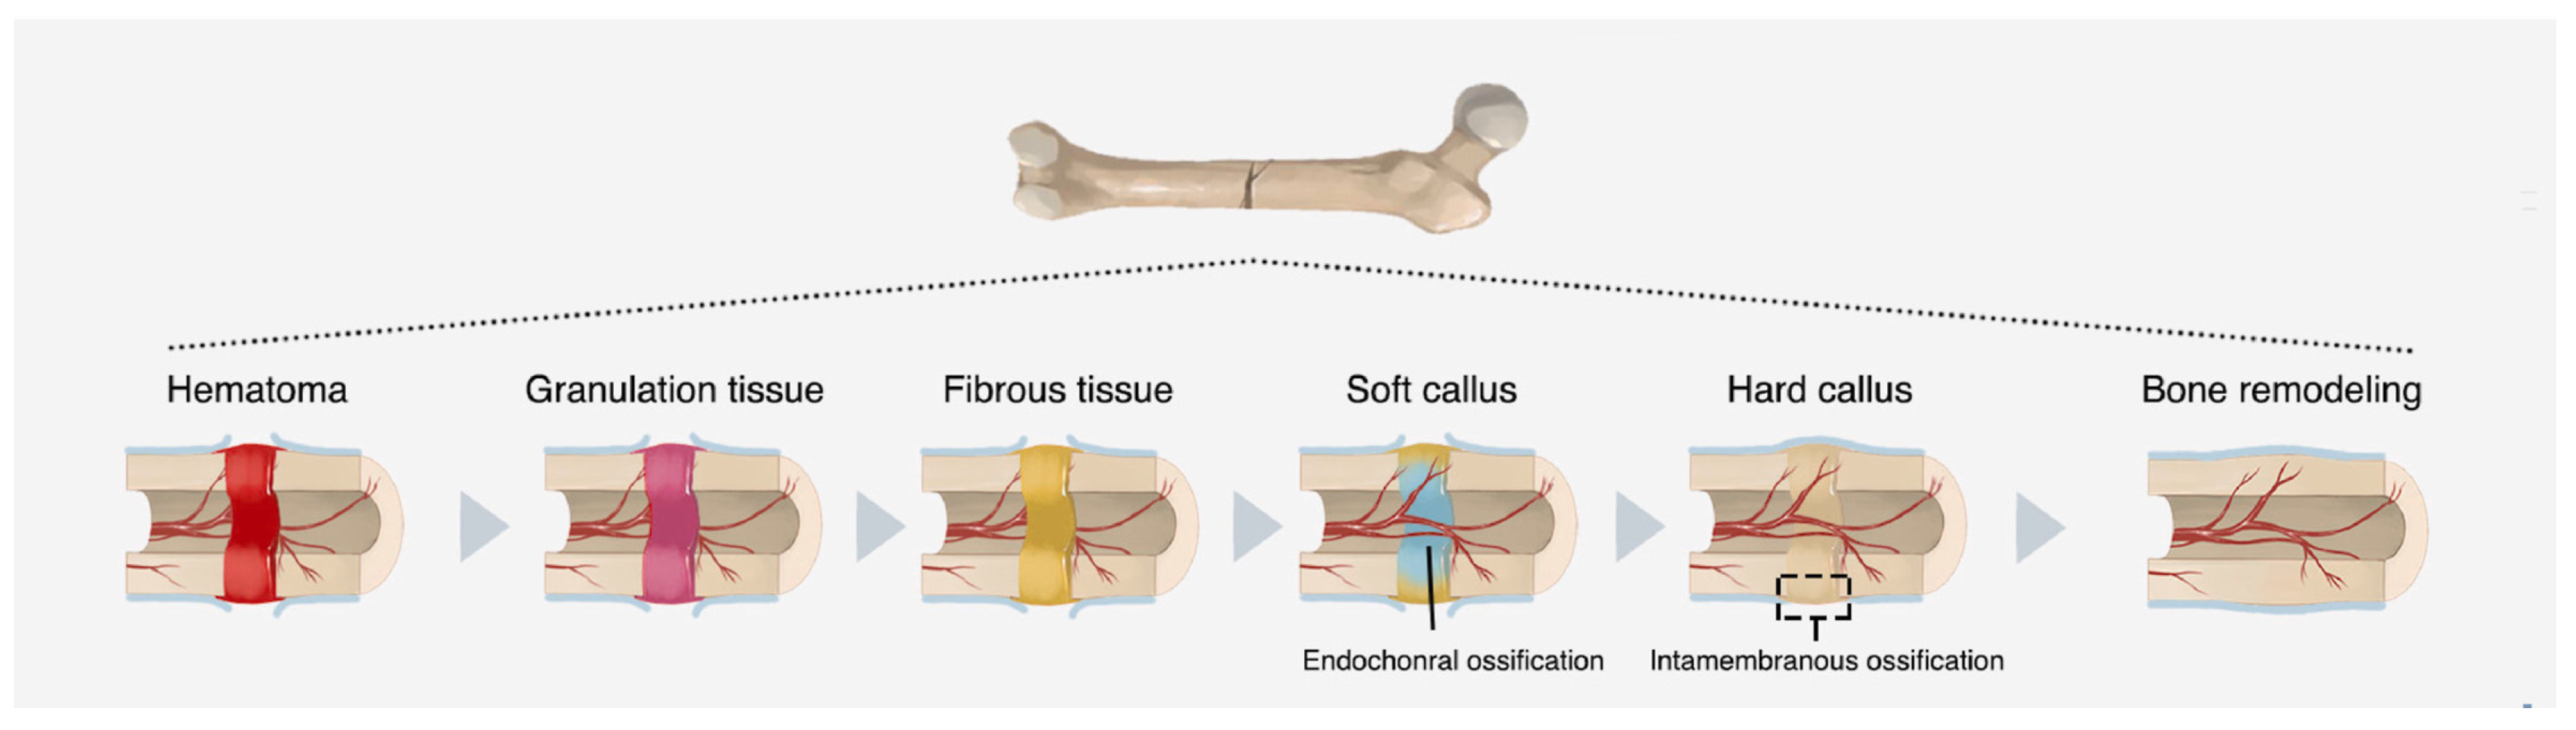

3. Soft Tissues Engineering

3.1. Wound Healing Mechanisms